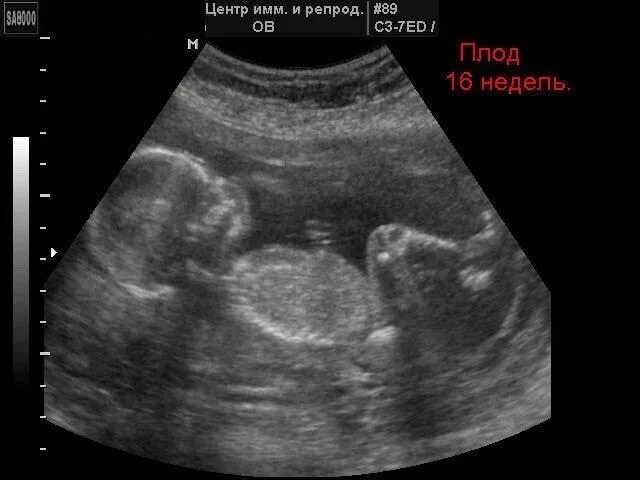

Как выглядит 16 неделя беременности фото